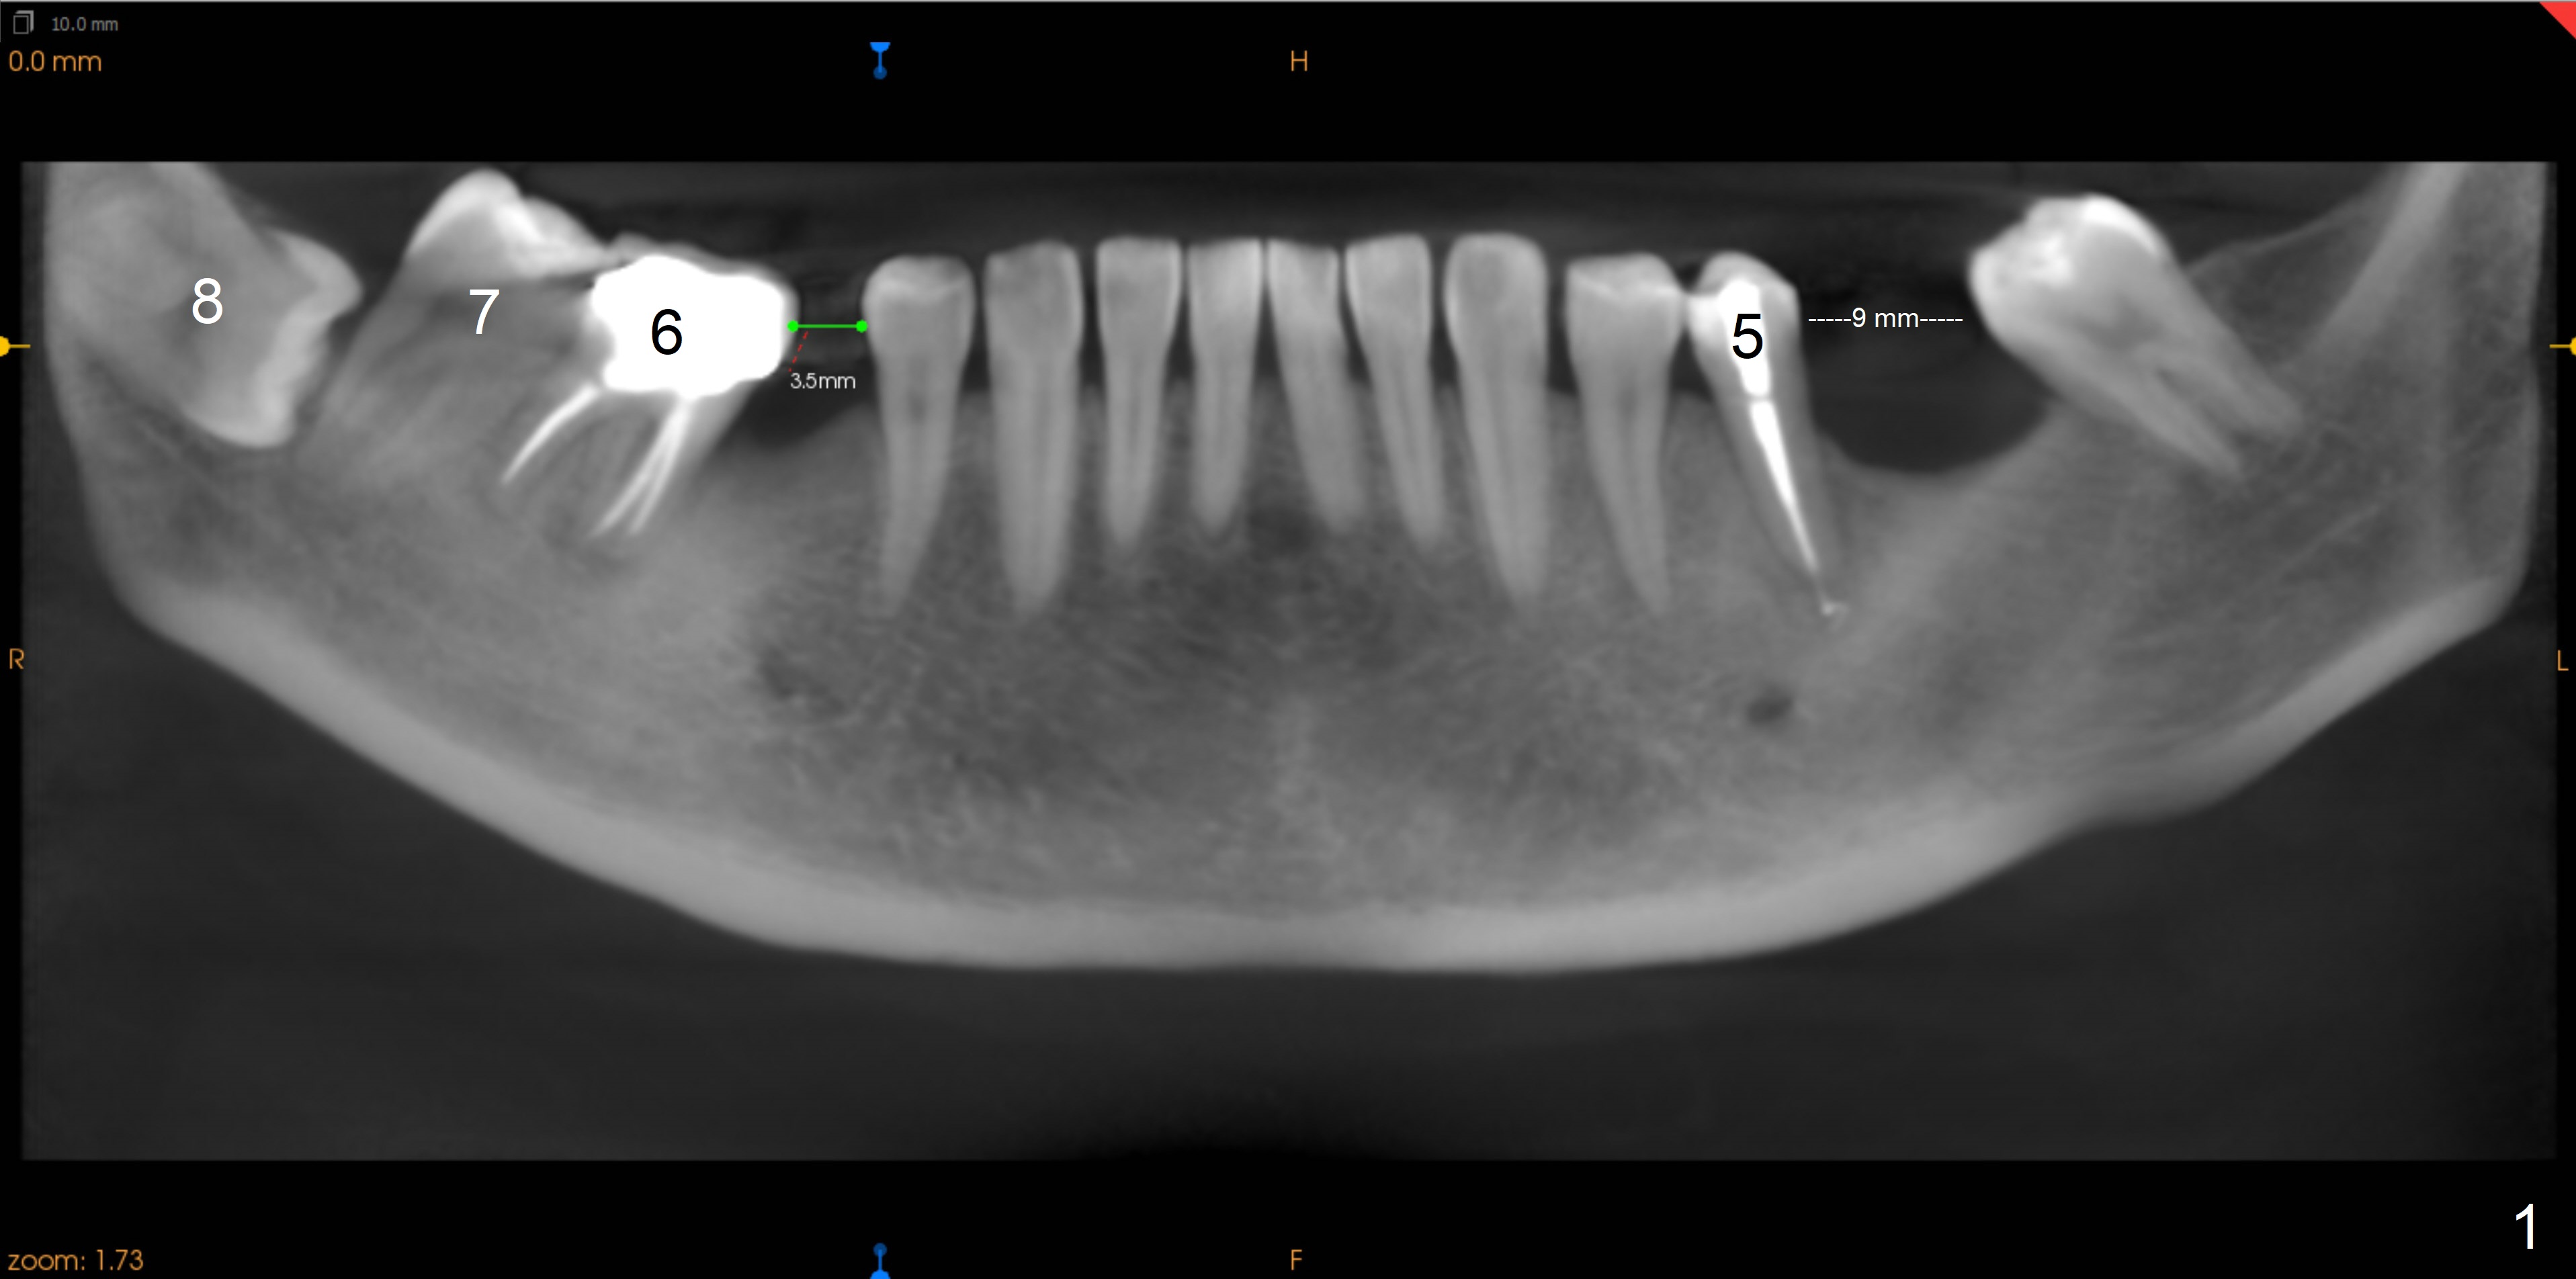

This panoramic X-ray is reconstructed from 3 D image (taken on 04/04/2018, Fig.1).  Uprighting LR6,7 involves extraction of LR8.  LL5 periapical lesion has been treated.  LL7 will be distalized 1-2 mm.